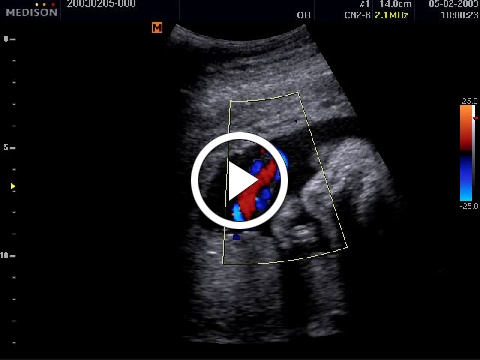

Példák a Cine memória tartalmának visszajátszására:

2. Color-mód Cine képei